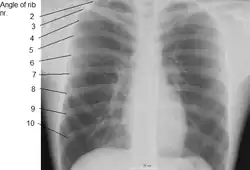

In vertebrate anatomy, ribs (Latin: costae) are the long curved bones which form the rib cage, part of the axial skeleton.[1] In most tetrapods, ribs surround the thoracic cavity, enabling the lungs to expand and thus facilitate breathing by expanding the thoracic cavity. They serve to protect the lungs, heart, and other vital organs of the thorax. In some animals, especially snakes, ribs may provide support and protection for the entire body.

Human ribs are flat bones that form part of the rib cage to help protect internal organs. Humans usually have 24 ribs, in 12 pairs.[2] 1 in 500 people have an extra rib known as a cervical rib. People may have a cervical rib on the right, left or both sides.[3] All are attached at the back to the thoracic vertebrae and are numbered from 1 to 12 according to the vertebrae to which they attach. The first rib is attached to thoracic vertebra 1 (T1). At the front of the body, most of the ribs are joined by costal cartilage to the sternum. Ribs connect to vertebrae at the costovertebral joints.[4]

Rib cage

The first seven sets of ribs, known as "true ribs", are attached to the sternum by the costal cartilages. The first rib is unique and easier to distinguish than other ribs. It is a short, flat, C-shaped bone, and attaches to the manubrium.[6] The vertebral attachment can be found just below the neck at the first thoracic vertebra, and the majority of this bone can be found above the level of the clavicle. Ribs 2 through 7 then become longer and less curved as they progress downwards.[7] The following five sets are known as "false ribs", three of these sharing a common cartilaginous connection to the sternum, while the last two (eleventh and twelfth ribs) are termed floating ribs.[2] They are attached to the vertebrae only, and not to the sternum or cartilage coming off of the sternum.

In general, human ribs increase in length from ribs 1 through 7 and decrease in length again through rib 12. Along with this change in size, the ribs become progressively oblique (slanted) from ribs 1 through 9, then less slanted through rib 12.[7]